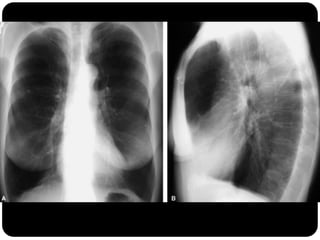

Atelectasia do Lobo Sup. D. (compare com slide

anterior que era consolidação de LSD!)

Atelectasia do LoboSup. D. (compare com slide anterior que era consolidação de LSD!)

Conceitos  Atelectasia: ausênciado ar alveolar;  Consolidação: substituição do ar alveolar (não há redução de volume);

 Quando ocorreessa consolidação os brônquios em seu interior podem tornar-se visíveis – broncograma aéreo.